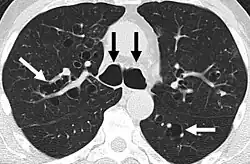

CT scan of the lungs showing findings diagnostic of bronchiectasis. White and black arrows point to dilated bronchi characteristic of the disease.

The goals of a diagnostic evaluation for bronchiectasis are radiographic confirmation of the diagnosis, identification of potential treatable causes, and functional assessment of the patient. A comprehensive evaluation consists of radiographic imaging, laboratory testing, and lung function testing.[63]

A chest X-ray is abnormal in most patients with bronchiectasis. Computed tomography is recommended to confirm the diagnosis and is also used to describe the distribution and grade the severity of the disease. Radiographic findings include airway dilation, bronchial wall thickening, and atelectasis.[65] Three types of bronchiectasis can be seen on CT scan, namely cylindrical, varicose, and cystic bronchiectasis.[66]